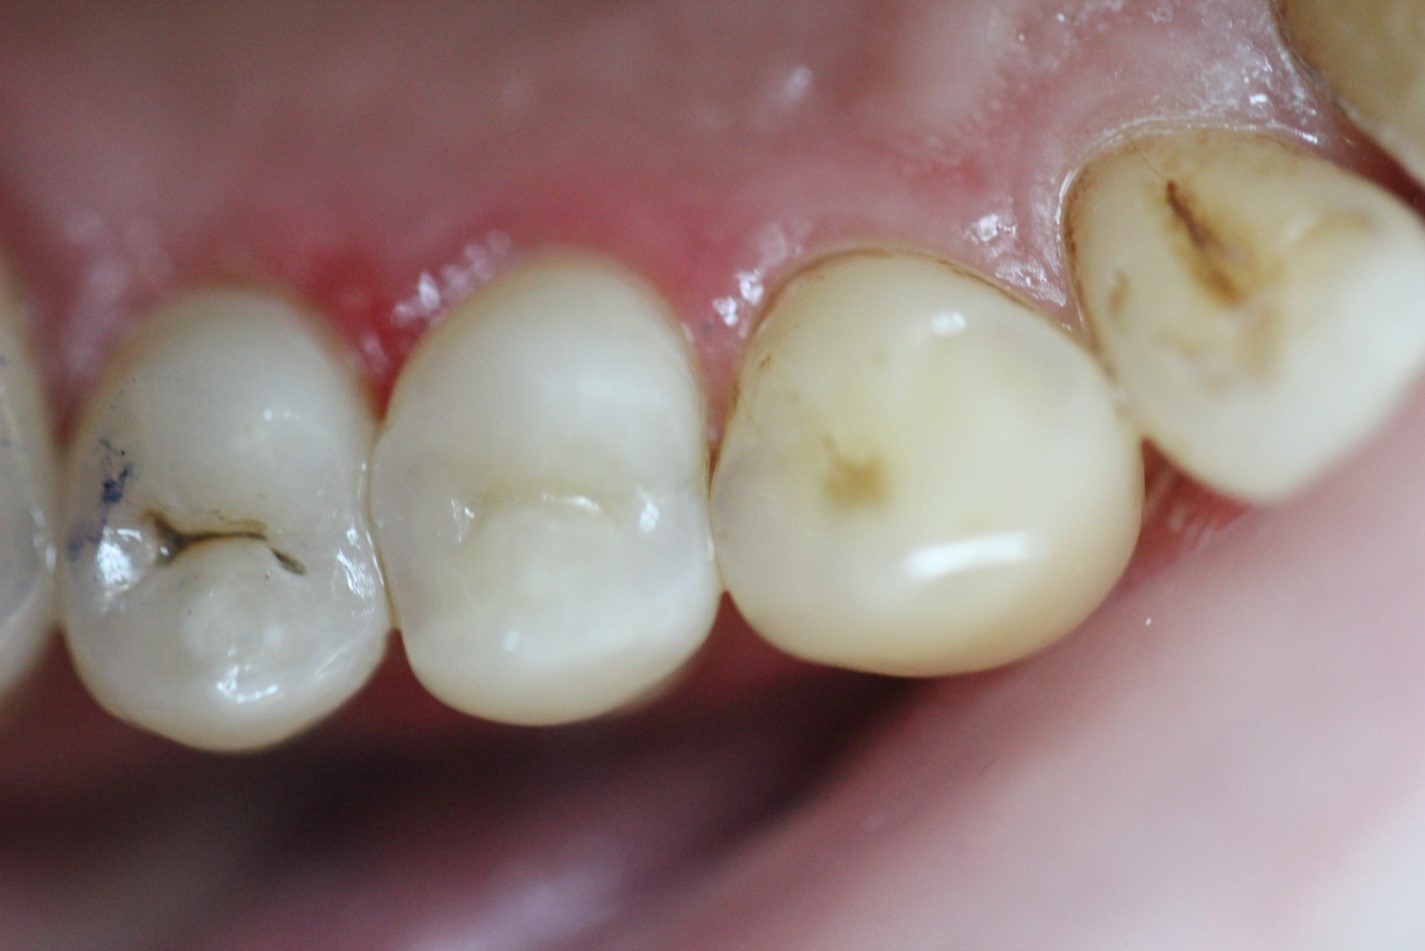

Поверхностный кариес

На фотографии изображён поверхностный кариес, который относится к необратимым процессам развития заболевания эмали зубов. Если кариес на ранней стадии можно лечить аппликациями фтора и кальция, то поверхностный кариес удаляется только при помощи пломбировочных материалов и использования бормашины.